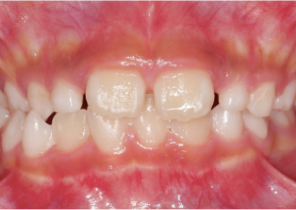

Étude de cas 1

10 ans et 0 mois, 18 étapes d’appareils d’expansion palatine Invisalign

Avec l’aimable autorisation de la Dre Sandra Khong Tai

Avant le traitement d’expansion avec les appareils d’expansion palatine Invisalign

Après le traitement d’expansion avec les appareils d’expansion palatine Invisalign

Après le traitement Invisalign First